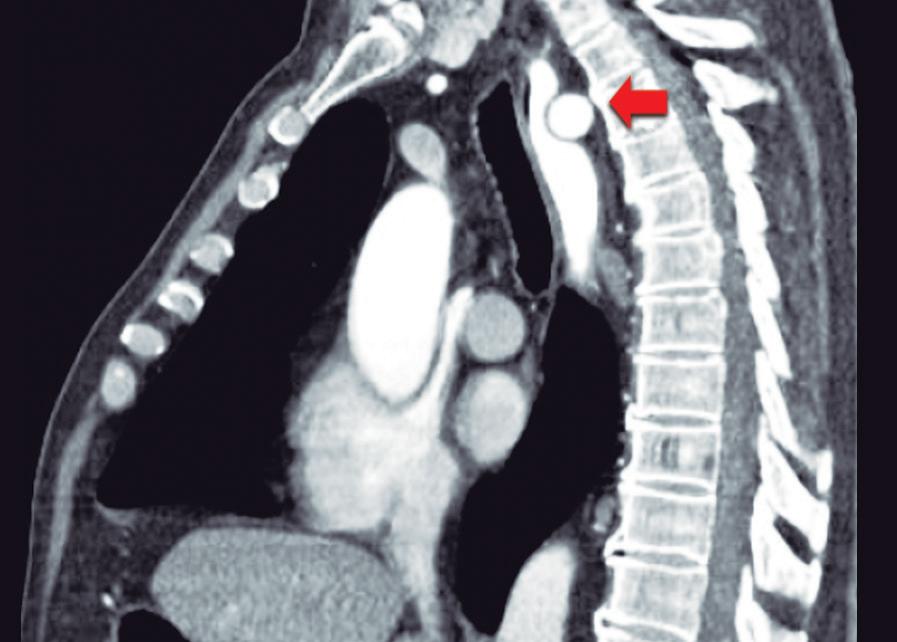

Paciente con vómitos en el periodo posoperatorio

Germán Francisco Rojas, Gabriel Adrián Mariño Camacho, Jesica Antonella Andruetto, Martín José Drago, Alejandro Moreira Grecco, Mariano Volpacchio, Esteban González Ballerga

Patient with Postoperative Vomiting